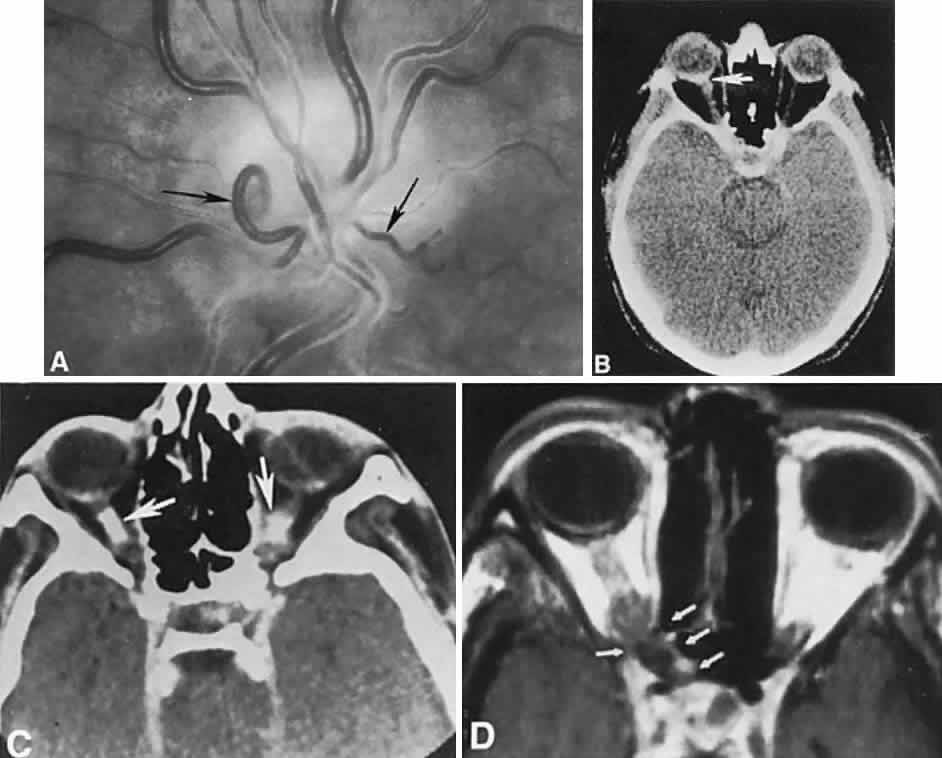

The retinal variety may be admixed in a person who suffers the more conventional attacks of migraine. It is presumed that vasospasm in the retinal circulation determines transient hypoxia, perhaps somewhat similar to the visual cortical event. On rare occasions, the fundus has been examined during typical retinal migraine episodes, and arterial constriction has been described. Wolter and Burchfield106 photographically documented such an episode and demonstrated mild “retinal edema”; vessel narrowing is also evident (Fig. 8). Fortunately, permanent complications of retinal migraine are rare. These may take the form of central retinal artery occlusion or ischemic papillopathy (see Volume 2, Chapter 16); nerve fiber bundle visual field defects may be demonstrated (Fig. 9).

Fig. 8. Retinal migraine. A. During amaurotic episode. Note the dusky appearance of the fundus, increased retinal sheen (possibly edema), and dark narrowed veins (arrows). The disc is also hyperemic. B. Fundus after episode. Compare paired arrows. (Courtesy of Dr. J. Reimer Wolter)